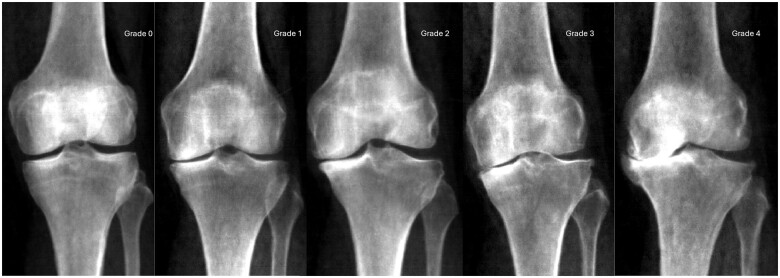

Methods: Right knee DXA scans were manually annotated for osteophytes to derive corresponding grades. Joint space narrowing (JSN) grades in the medial joint compartment were determined from automatically measured minimum joint space width. Overall rKOA grade (0-4) was determined by combining osteophyte and JSN grades. Logistic regression was employed to investigate the associations of osteophyte, JSN and rKOA grades with knee pain and hospital-diagnosed KOA. Cox proportional hazards modelling was used to examine the associations of these variables with risk of subsequent total knee replacement (TKR).

Results: Of the 19 595 participants included (mean age 63.7 years), 19.5% had rKOA grade ≥1 (26.1% female, 12.5% male). Grade ≥1 osteophytes and grade ≥1 JSN were associated with knee pain, hospital-diagnosed KOA and TKR. Higher rKOA grades were linked to stronger associations with these clinical outcomes, with the most pronounced effects observed for TKR. Hazard ratios for the association of rKOA grades with TKR were 3.28, 8.75 and 28.63 for grades 1, 2 and 3-4, respectively.